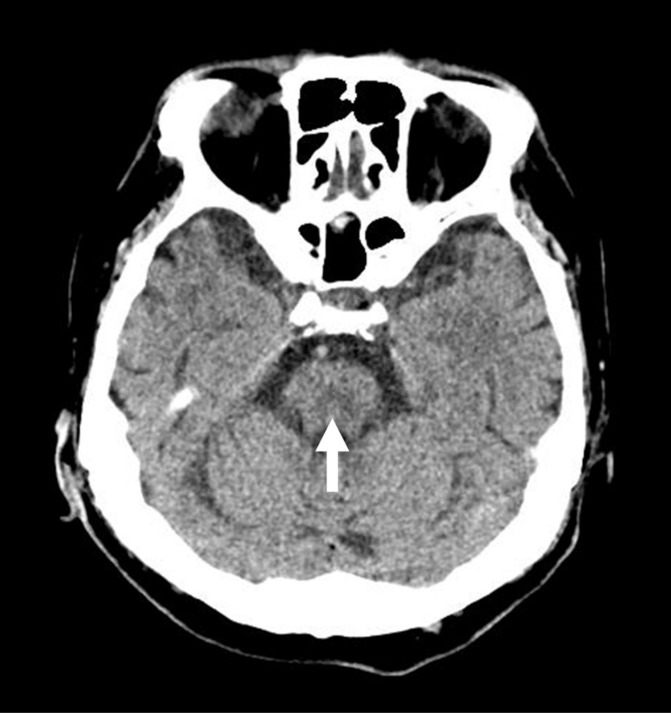

Hyponatremia is a common electrolyte disorder requiring careful management to prevent severe complications. Osmotic demyelination syndrome (ODS) is a serious neurological disorder that can develop from rapid correction of hyponatremia. Herein, is a description of the case of a 61-year-old man with multiple risk factors, including alcoholism, hypokalemia, malnutrition, and alcoholic liver cirrhosis, who developed ODS despite adherence to the recommended correction rate for hyponatremia. The patient presented to the emergency department with generalized weakness, gait disturbance, and decreased muscle strength. Initial laboratory investigations revealed severe hyponatremia, hypokalemia, and dehydration. The patient was treated with cautious correction of the hyponatremia below 8 mmol/L per day. However, on the seventh hospital day, he developed tremors, rigidity, and decreased consciousness and was diagnosed with osmotic demyelination syndrome. Despite receiving general supportive care, desmopressin, and dextrose 5% in water to reduce the serum sodium levels, the patient did not show significant improvement and was transferred to a nursing home for long-term conservative care on day 35 of hospitalization. This case report highlights the challenges associated with the diagnosis and management of osmotic demyelination syndrome and the importance of identifying patients at high risk of developing this neurological disorder.

Abstract Image